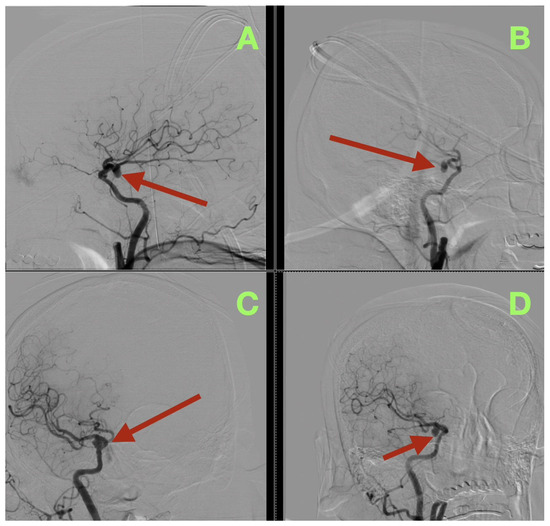

At the three-month follow-up evaluation, the patient reported resuming all of her daily activities without experiencing recurrent severe headache, confusion, or seizure-like episodes. The patient’s neurological examination was normal (all cranial nerves intact; pupils equal/reactive; normal eye movements without ptosis/diplopia; strength 5/5; stable gait; normal coordination). The patient’s MoCA score was 28/30. The patient’s functional outcome was mRS 0, and her Barthel Index was 100. Three-month CT angiography (Figure 4A–C) demonstrated complete aneurysm exclusion, a reconstructed patent carotid–PCom junction without parent vessel stenosis, no clip migration, and robust filling of the fPCA via the preserved PCom. There was no evidence of chronic ischemia, and the CSF spaces were restored without hygroma or hydrocephalus.

Figure 4.

Three-month postoperative control CT angiography. (A) Axial source image at the level of the skull base demonstrates the aneurysm clip at the right carotid–posterior communicating junction (arrow), with stable positioning and no surrounding hypodensity, hemorrhage, or parenchymal distortion. The adjacent temporal and basal frontal regions show preserved attenuation, without signs of delayed ischemic injury. (B) Coronal reconstruction confirms durable anatomical restoration of the parasellar and suprasellar region (arrow), with normal ventricular configuration and no evidence of hydrocephalus, mass effect, or clip-related compromise of adjacent structures. (C) Sagittal reconstruction localizes the clip construct along the reconstructed carotid–posterior communicating complex (arrow), illustrating maintained skull-base anatomy, absence of clip migration, and stable postoperative remodeling of the surgical corridor.